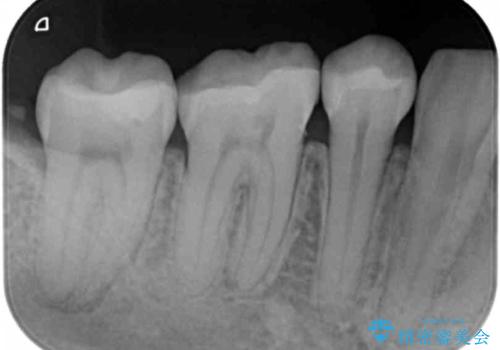

- 矯正後の検査で歯と歯の間の虫歯が確認された患者様です。

虫歯の除去後、セラミックインレーで修復していきます。

- 右下5 セラミックインレー 77,000円費用は治療当時の料金となります

レントゲン画像からは読み取りづらいですが、視診にて歯の一部が黒く透けているのが確認できました。

小さな虫歯でも見落とさずに精度の良い修復をすることで二次う蝕のリスクを減らすことができます。